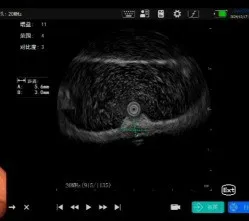

近日,UG环球国际附属第二医院消化内科门诊接诊了一位患者,在外院行普通胃镜检查提示胃粘膜下隆起,经人介绍患者来我院寻医诊治,张又莉副主任接诊后为该患者行小探头超声内镜检查,成功检出并定性诊断病灶。

左:普通胃镜;右:超声内镜